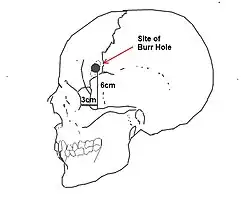

Lobotomie (ook wel: leukotomie) is een chirurgische operatie die rond het midden van de 20e eeuw werd toegepast. Tijdens de ingreep wordt de verbinding van het voorhoofdsgedeelte van de hersenen en de rest van de hersenen en het zenuwstelsel door een insnijding bijna geheel verbroken. De chirurg boorde eerst twee gaten in de schedel van de plaatselijk verdoofde patiënt en maakte de incisie in de hersenen. Later ontstond een snellere, 'transorbitale' methode zonder boren: een instrument werd onder plaatselijke verdoving boven de oogbol, onder het ooglid door, de schedel in gedreven en dan in de hersenen heen en weer bewogen.

De eerste systematische experimenten door de neuroloog António Egas Moniz en de chirurg Almeida Lima van de Universiteit van Lissabon dateren van 1935, waarbij de frontale cortex en de rest van de hersenen werd doorgesneden. De resultaten waren tamelijk goed, in het bijzonder bij de behandeling van ernstige depressie, hypochondrie, en angst- of dwangstoornissen, hoewel sterke persoonlijkheidsveranderingen optraden en 4 procent van de patiënten de operatie niet overleefde.[5] Ondanks deze risico's werd de methode vooral in de VS met enthousiasme begroet als behandelwijze voor anders onbehandelbare aandoeningen. Rond 1937 hadden Moniz en de zijnen zo'n 40 lobotomieën uitgevoerd en werd het een beroepsstandaard. Moniz kreeg in 1949 zelfs een Nobelprijs.[6] Zijn methode wordt doorgaans 'lobotomie' genoemd, hoewel dit eigenlijk een term is voor een breder scala aan chirurgische procedures.

Lobotomie werd in de Verenigde Staten op grotere schaal toegepast met gebruik van een nieuwe techniek die ontwikkeld was door Walter Freeman. Hij bedacht de transorbitale lobotomie, een methode zonder schedelboring. De patiënt werd eerst met een elektroshock bewusteloos gemaakt, vervolgens werd een ijspriem via een oogkas zeven centimeter diep de hersenen in geslagen.[7][8] Vanaf 1945 tot 1960 prees hij orbitale lobotomie aan als effectieve behandelmethode. De nieuwe, relatief eenvoudige ingreep duurde nog maar een paar minuten en kon overal, ook buiten een operatiekamer, worden uitgevoerd. Hierdoor werd de lobotomie enige tijd gezien als een algemeen bruikbare behandelmethode voor allerlei problemen, zoals zelfs wangedrag van kinderen. Uiteindelijk hebben in de VS ca. 40.000, in het Verenigd Koninkrijk ca. 17.000 en in Scandinavië ca. 9300 mensen deze specifieke operatie ondergaan, zonder dat er serieus wetenschappelijk onderzoek naar de effectiviteit van de methode was gedaan.